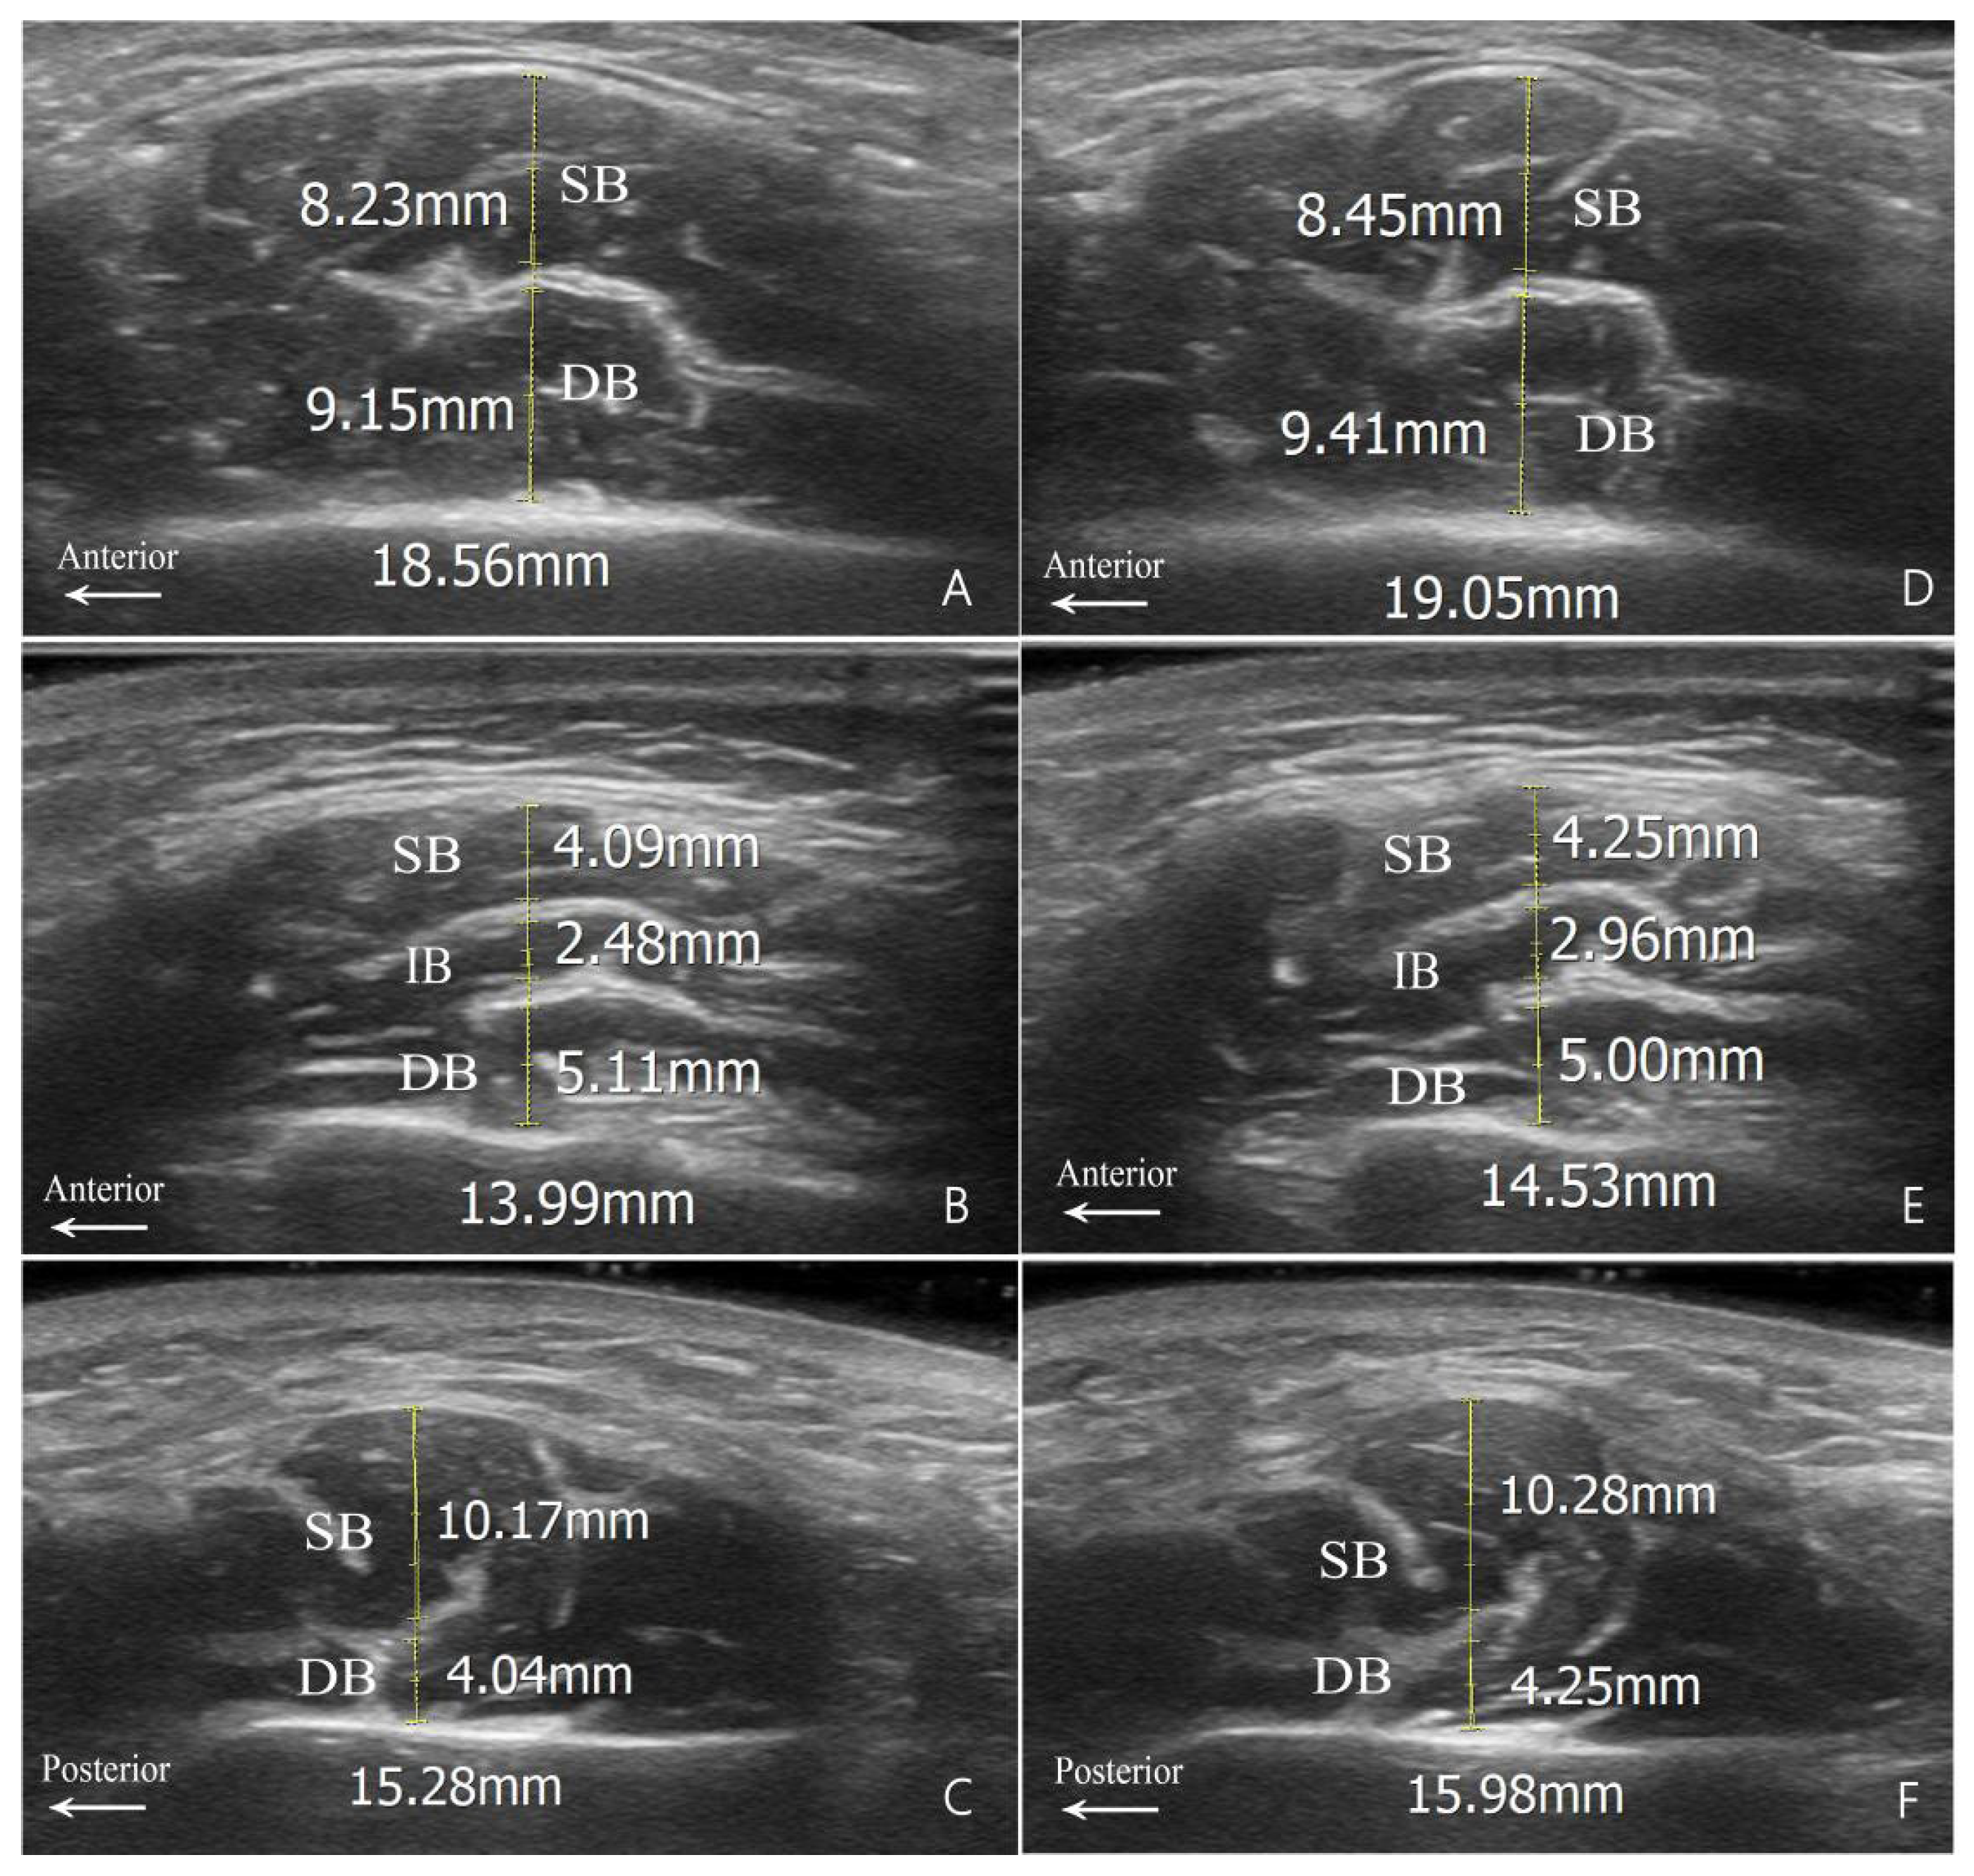

2.3. DIT-Based Analysis of the Masseter Muscle Thickness

5.2.3. US-Based Analysis of the Masseter Muscle Thickness